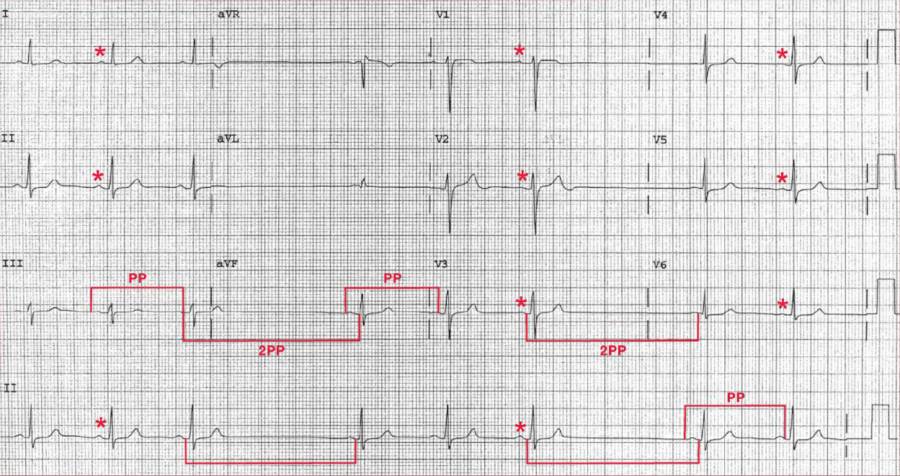

The rhythm is primarily regular at a rate of 60 bpm. There are P waves (*) before each QRS complex with a stable PR interval (0.16 sec).

There are two long RR (or PP) intervals without any P wave during the intervals (U). These represent two sinus pauses, the duration of which is equal to two sinus intervals (n) (based on measurement of the PP intervals of the two sinus complexes immediately before and after the pauses). Therefore, this represents sinus node exit block.

The QRS complex duration (0.08 sec) and morphology are normal. The axis is normal, between 0° and +90° (positive QRS complex in leads I and aVF). The QT/QTc intervals are normal (400/400 msec).

With sinus node exit block, the sinus impulses are regular but there is a failure of one sinus impulse to exit the sinus node area to activate the atria; hence no P wave is present. Since the sinus node impulses are regular, the PP interval around the pauses is equal to two sinus intervals.